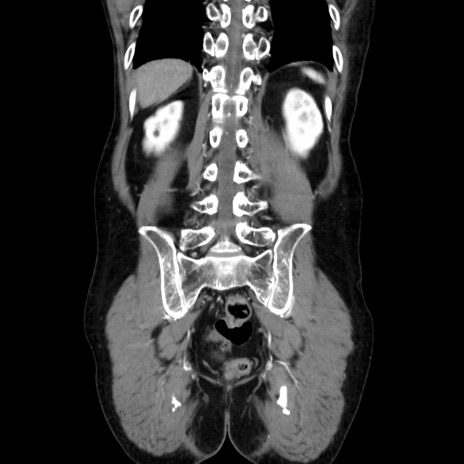

症例37(冠状断像)

【症例】40歳代 男性

【主訴】腹痛

【現病歴】4時間ほど前に電車に乗車中に臍部上より腹痛出現。徐々に増悪し起立困難となり、救急外来受診。生ものは数日食べていない。今朝お雑煮を食べた。

【身体所見】BT 36.8℃、BP 117/84mmHg、HR 91/min、SpO2 97%、苦悶様、腹部:臍上部広範囲圧痛あり、反跳痛±

【データ】WBC 8100、CRP 0.03